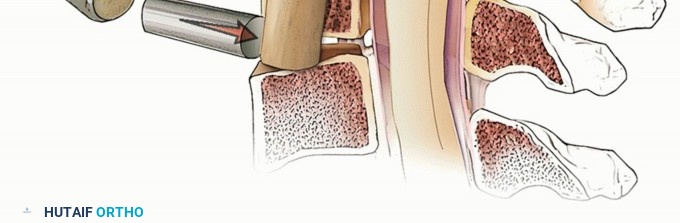

TECH FIG 1 • (continued) C. At the level of the disc space, a wider decompression may be necessary for satisfactory root decompression (yellow lines). Staying within the uncinates will allow for thorough decompression while avoiding vertebral artery injury, unless a vertebral artery anomaly exists. Such anomalies are more likely to occur within the vertebral body rather than the disc spaces, and they should be recognized on preoperative imaging to avoid injury. 2. ## Cervical Corpectomy The edges of the corpectomy are longitudinally delineated with a high-speed burr from uncinate to uncinate to define the safe limits of the decompression. Next, a Leksell rongeur can be used to quickly remove large fragments of vertebral body bone (TECH FIG 2). This bone should be saved for grafting. Once the cancellous bone is removed grossly, fine decompression then proceeds with a high-speed burr. Under direct visualization, a high-speed burr is used to remove bone until a thin shell of posterior cortex remains. Microcurettes and Kerrisons are then used to flake off the remaining bone.

### TECH FIG 2 • Steps in bone removal. A. Leksell rongeur is used to remove large pieces of vertebral body bone after delineating the lateral edges of the corpectomy longitudinally along the medial border of the uncinates with a high-speed burr. B. After removing the bulk of the vertebra, a burr is used to sequentially remove bone in layers until only a thin remnant of bone remains. C. Finally, curettes and Kerrison rongeurs are used to remove the remaining bone. Adequate thinning of all bone to be removed allows the passage of smaller instruments that do not exert pressure on the spinal cord. Attention should be paid to maintaining the width of the corpectomy as it proceeds posteriorly toward the canal, as the tendency is to cone the decompression narrowly as one proceeds posteriorly. Vertebral body bleeding often hinders visualization during bone removal. The surgeon should take time to achieve hemostasis using bone wax (gently applied when the remaining vertebra is still thick) or powdered Gelfoam-thrombin (when the remnant vertebral body is very thin). Significant dorsal pressure should be avoided during these maneuvers to avoid inadvertently plunging into the spinal canal. Epidural bleeding is best controlled with bipolar cautery as well as Gelfoam-thrombin. 3. ## Removing the Posterior Longitudinal Ligament